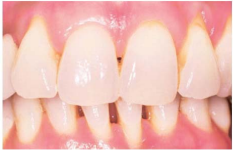

60.如圖所示,為牙周炎患者治療後一段時間,其前牙22頰側觀顯示牙齦有牙菌膜、探測深度<3 mm、探針沿牙齦周邊滑過會有流血現象、附連喪失量4 mm, 沒有持續增加,下列有關此顆牙的 敘述何者錯誤?

(A)診斷為牙菌斑誘導牙齦炎 (B)診斷為慢性牙周炎 (C)根據1967 Löe學者的牙齦指數(gingival index)為2 (D)治療方式只須加強口腔衛生即可